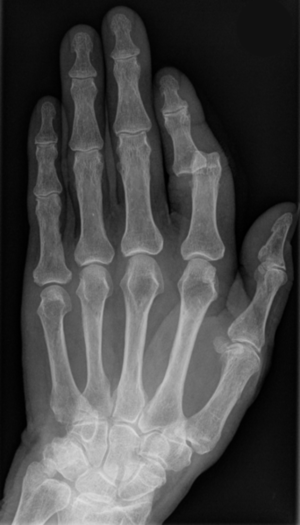

Röntgenbild eines ausgerenkten Zeigefingers - Hellerhoff commons.wikimedia.org, CC BY-SA 3.0

Bei einer Verrenkung oder Ausrenkung kommt es zu einer Verschiebung zweier durch ein Gelenk verbundener Knochenenden.

Dabei können die Gelenkpartner oft nicht mehr in die normalen Gelenkstellungen zurückkehren.

Als Folge entstehen Kapsel- und Bandzerreißungen.